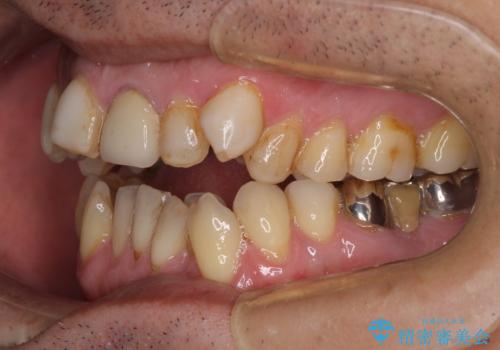

- 長年気になっていた口元を改善したいとのことで来院された患者様です。

外科手術を併用した矯正治療を検討するほどに隙間の空いた開咬と、顕著な叢生が認められました。

開咬の改善には、舌の突出癖改善のためにトレーニングを行いつつ、インビザラインでの矯正治療が大変有効ですが、上顎骨が下顎骨に対して前方位に位置しており、インビザライン単独で治療を行うよりは補助装置とワイヤー矯正で奥歯の咬み合わせを改善してから、開咬改善のためのインビザライン矯正治療を行うこととしました。

奥歯の銀歯は、土台の一部に抜歯が必要であったので、矯正治療の途中で抜歯してからオールセラミックブリッジによる補綴治療を行うこととしました。